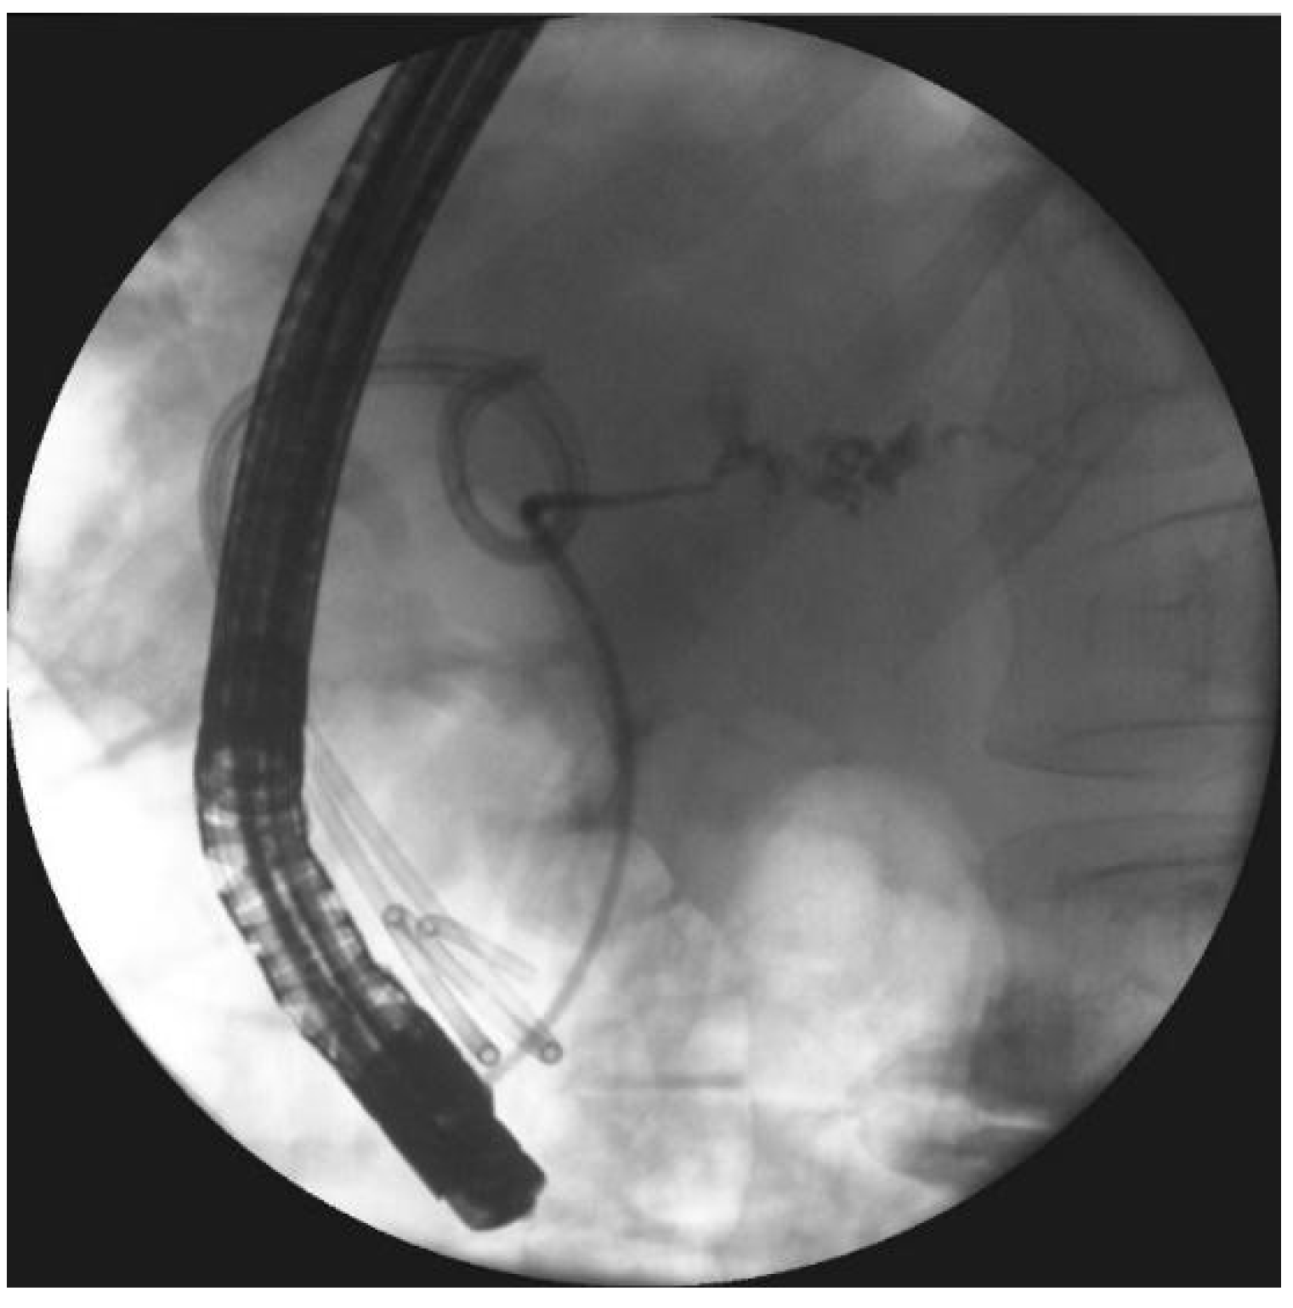

- Smoczyński, M.; Jagielski, M.; Siepsiak, M.; Adrych, K. Endoscopic necrosectomy through the major duodenal papilla under fluoroscopy imaging. Arch. Med. Sci. 2018, 14, 470–474. [Google Scholar] [CrossRef] [PubMed]

| Endoscopic necrosectomy under fluoroscopic guidance (endoscopic debridement) | Procedure that enable to remove necrotic tissues from necrotic cavity through transmural fistula under fluoroscopy with use of various types of endoscopic tools. Indication for endoscopic debridement is WOPN containing poorly-liquefied necrotic tissues. |